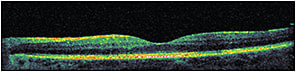

At the first visit, ordering OCT (particularly when best-corrected visual acuity is less than 20/20) is important because it will help us to document and learn about the pattern, location, thickness (Figures 1 and 2), and vitreomacular interface status of the edema, all of which can affect our treatment plan and visual prognosis.

Figure 1. Pretreatment OCT of diabetic macular edema.

OCT can be ordered again after 18 weeks based on treatment plan (Figures 3 and 4), to monitor the effectiveness of treatment. Further, it can help us decide whether it is mandatory to change, stop, or continue with the treatment plan.

Figure 3. The same patient as in Figures 1 and 2, following four anti-VEGF injections.